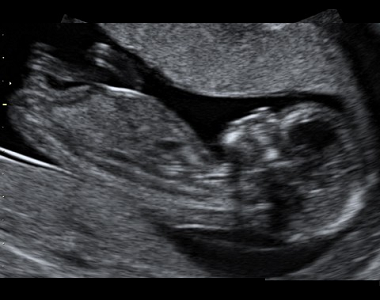

Zhruba nejpozději do konce prvního trimestru žena obdrží těhotenskou průkazku. Jedná se o nejdůležitější dokument v těhotenství, který by žena měla mít stále u sebe. Do schématu jednotlivých návštěv v těhotenské poradně, která mají v počátku interval 4-6 týdnů, jsou zahrnuta i tři ultrazvuková vyšetření. První v 11. až 13. týdnu těhotenství, sloužící k určení termínu porodu dle velikosti plodu, ale i vývojových vad plodu. Druhé ve 20. až 22. týdnu těhotenství, které je zaměřeno na velikost plodu, určení množství plodové vody, uložení placenty, pohybů plodu a také vývojových vad. Obdobně pak třetí ultrazvuk mezi 30. až 32. týdnem těhotenství.

Ultrazvuk

V průběhu těhotenství se provádí ultrazvuková vyšetření za účelem screeningu vývojových vad. Kdy jednotlivá vyšetření probíhají a co znamenají zkratky...